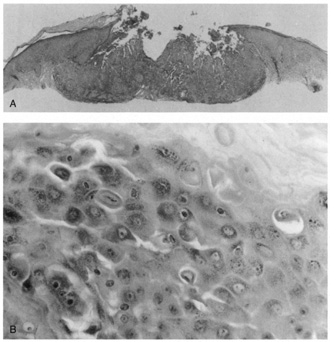

Lesions of molluscum contagiosum often affect the periorbital and lid skin as 1- to 3-mm domeshaped papules with a small central dell. This large pox virus multiplies in the cytoplasm, and, histologically, homogeneous purple intracytoplasmic inclusion bodies (molluscum bodies) are seen in an acanthotic epidermis (see Fig. 7).

Fig. 7. Molluscum Contagiosum—A. Umbilicated lesions typical of molluscum contagiosum on the upper lid of a child. Infection near the edge of the lid may cause a toxic follicular conjunctivitis. B. Low-power photomicrograph demonstrating crater shape of excised lesion (hematoxylin and eosin stain). C. High-power photomicrograph illustrating the large clumps of eosinophilic viral inclusions in the epithelial cells (“molluscum bodies“) (hematoxylin and eosin stain). (Photos courtesy of William Morris, M.D.)